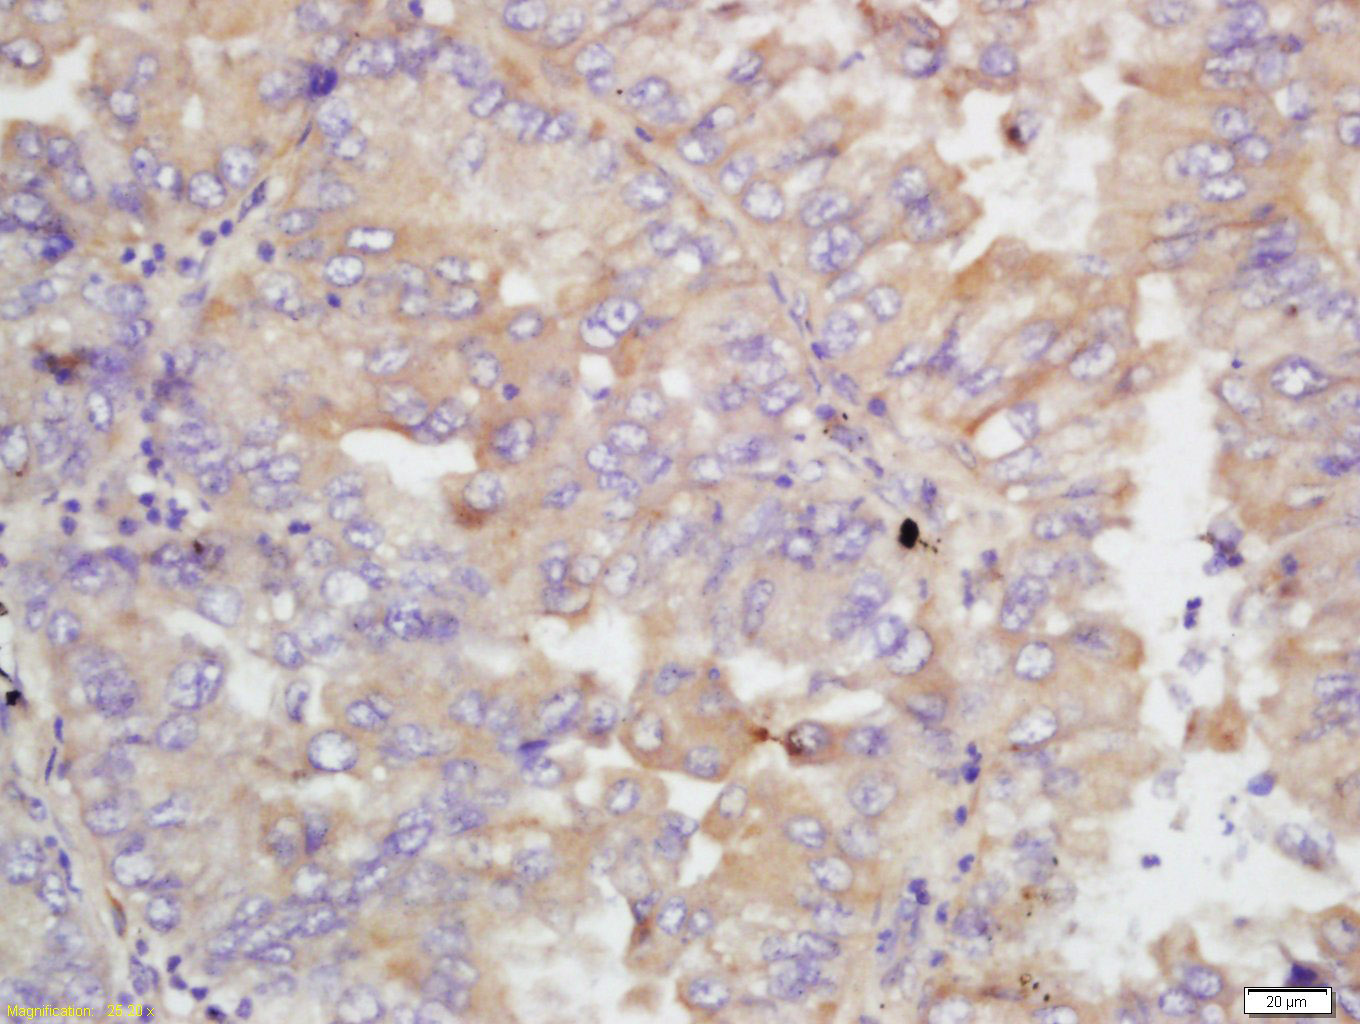

Tissue/cell: human lung carcinoma; 4% Paraformaldehyde-fixed and paraffin-embedded; Antigen retrieval: citrate buffer ( 0.01M, pH 6.0 ), Boiling bathing for 15min; Block endogenous peroxidase by 3% Hydrogen peroxide for 30min; Blocking buffer (normal goat serum,C-0005) at 37℃ for 20 min; Incubation: Anti-MGLAP Polyclonal Antibody, Unconjugated(bs-4315R) 1:200, overnight at 4°C, followed by conjugation to the secondary antibody(SP-0023) and DAB(C-0010) staining